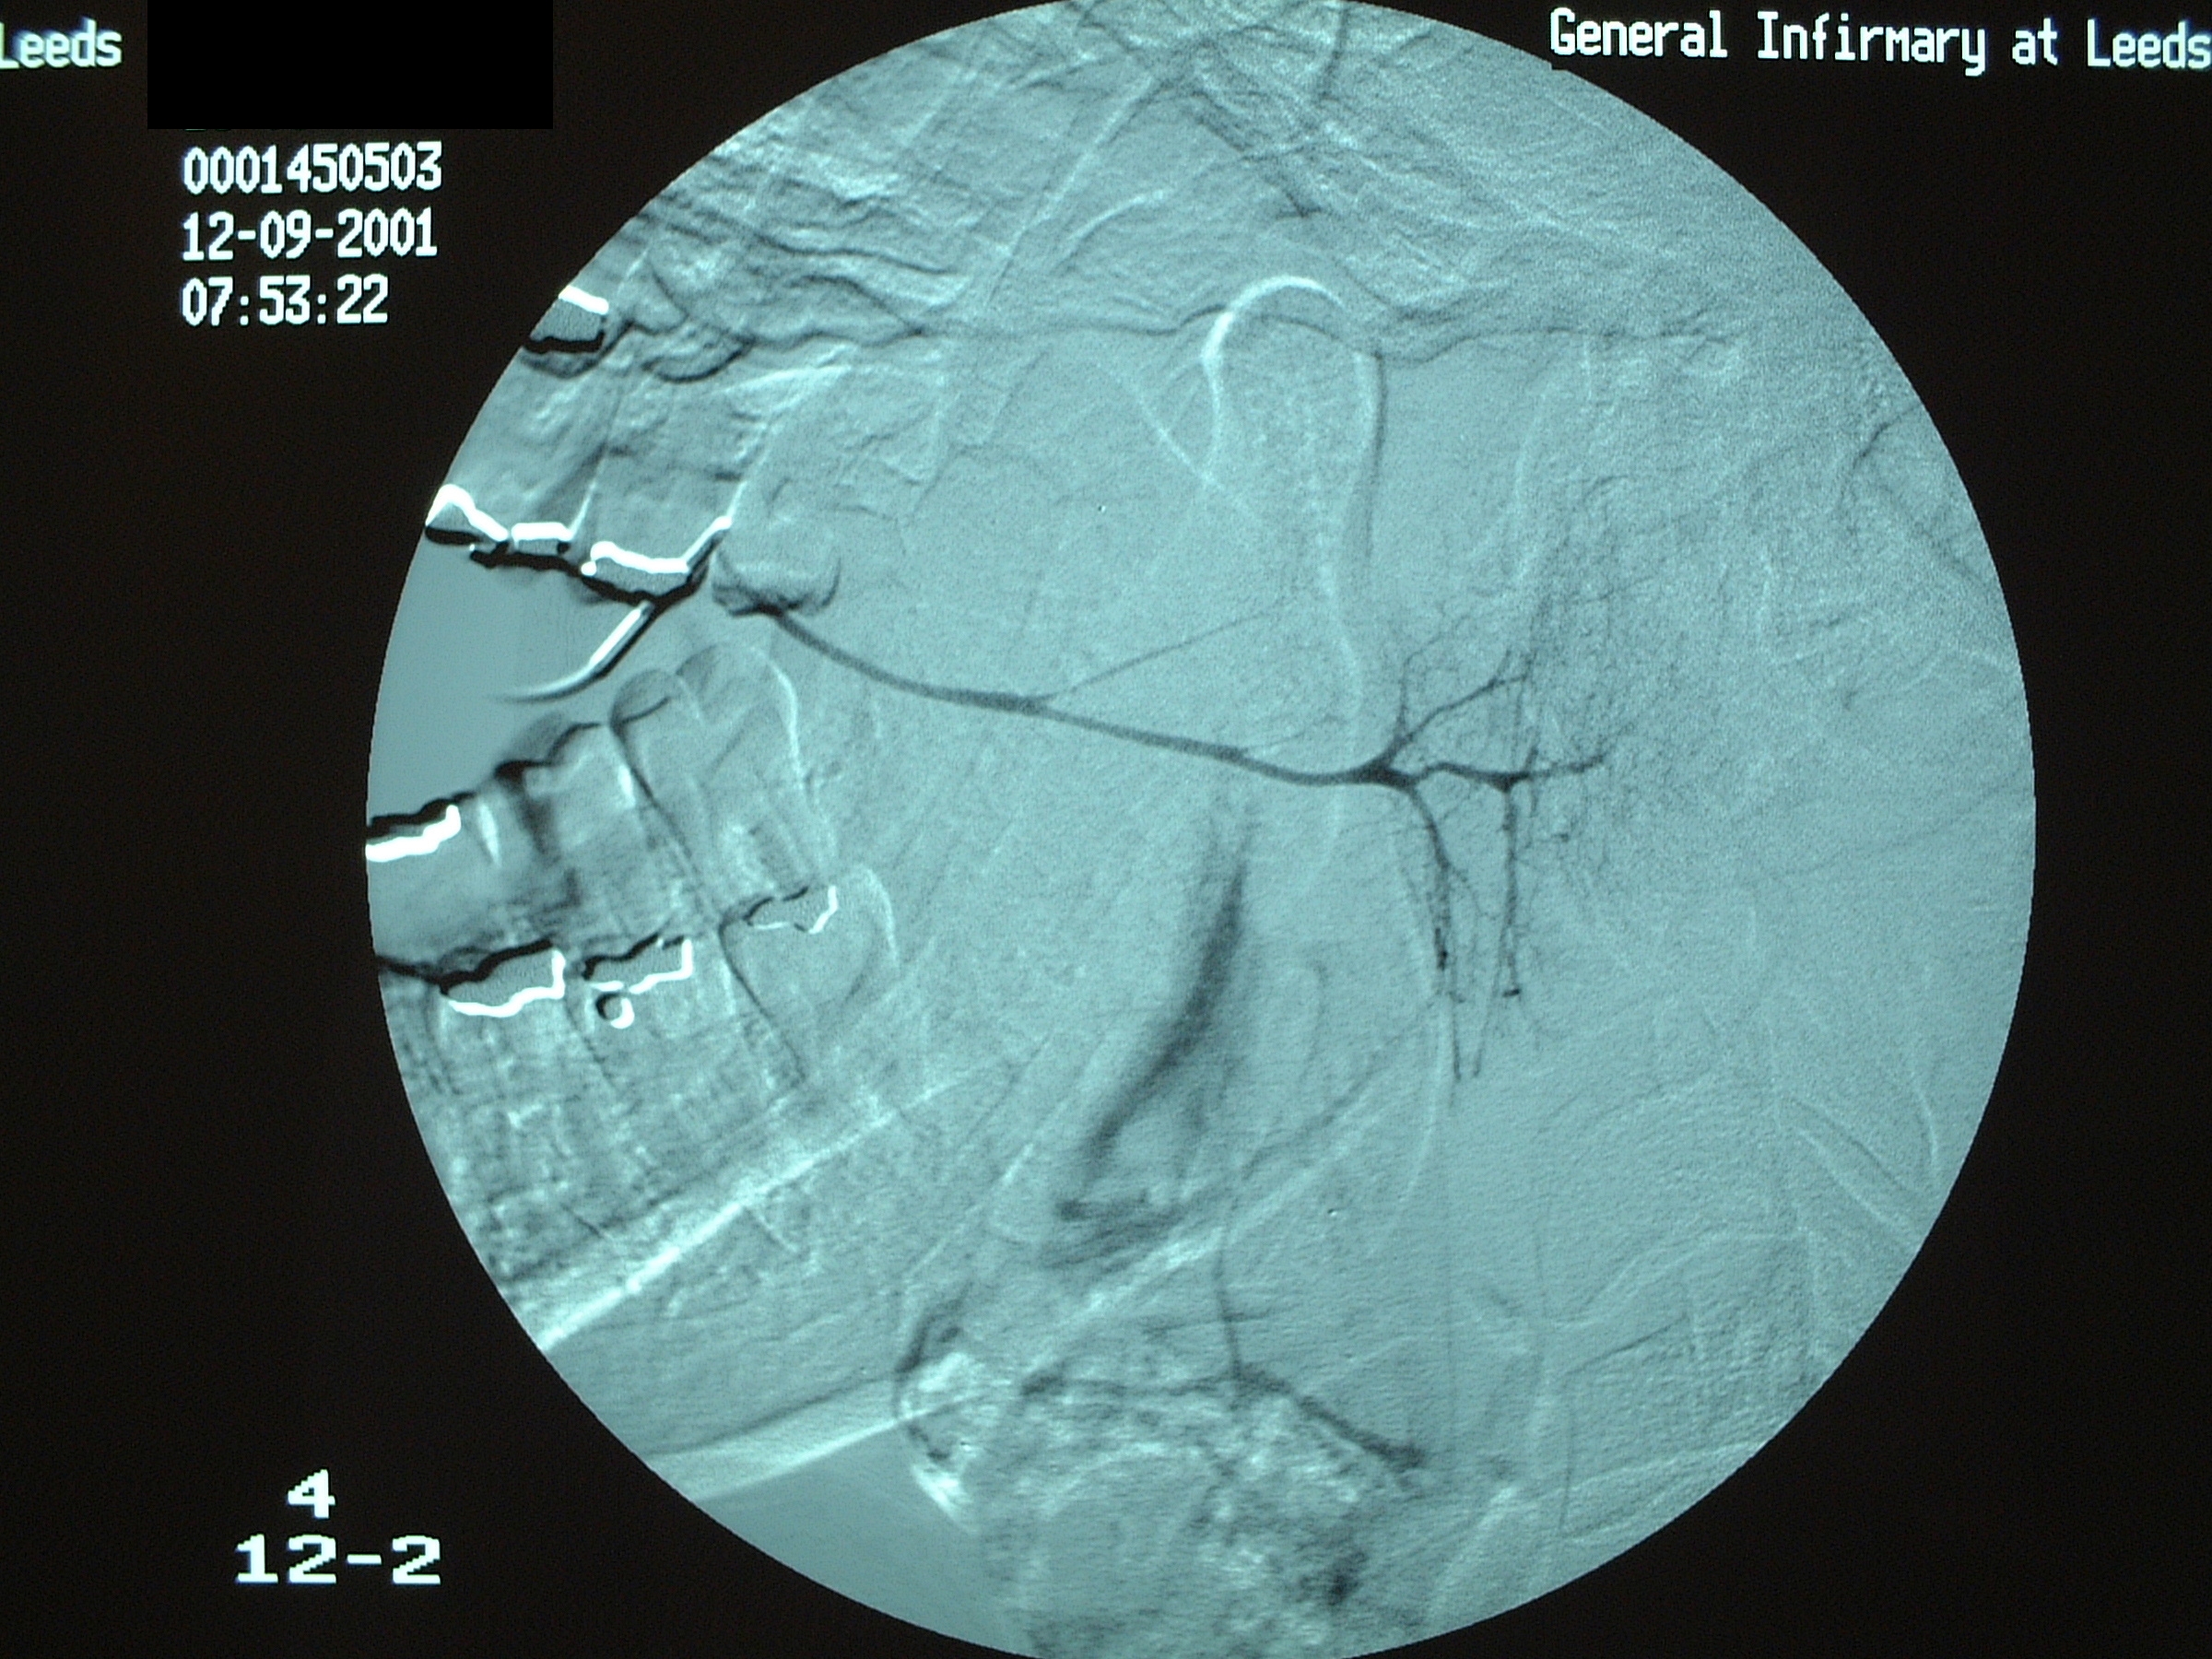

In the duct, a calculus is date shaped, at the junction of duct and gland it is comma shaped and in the gland it is round. Should a calculus not be visible on plain X-ray images, a sialogram is required which may demonstrate a radiolucent stone, a mucus plug or a stricture in the duct (see Figure 3).

Figure 3: A siaologram. These images are useful diagnostically and therapeutically.